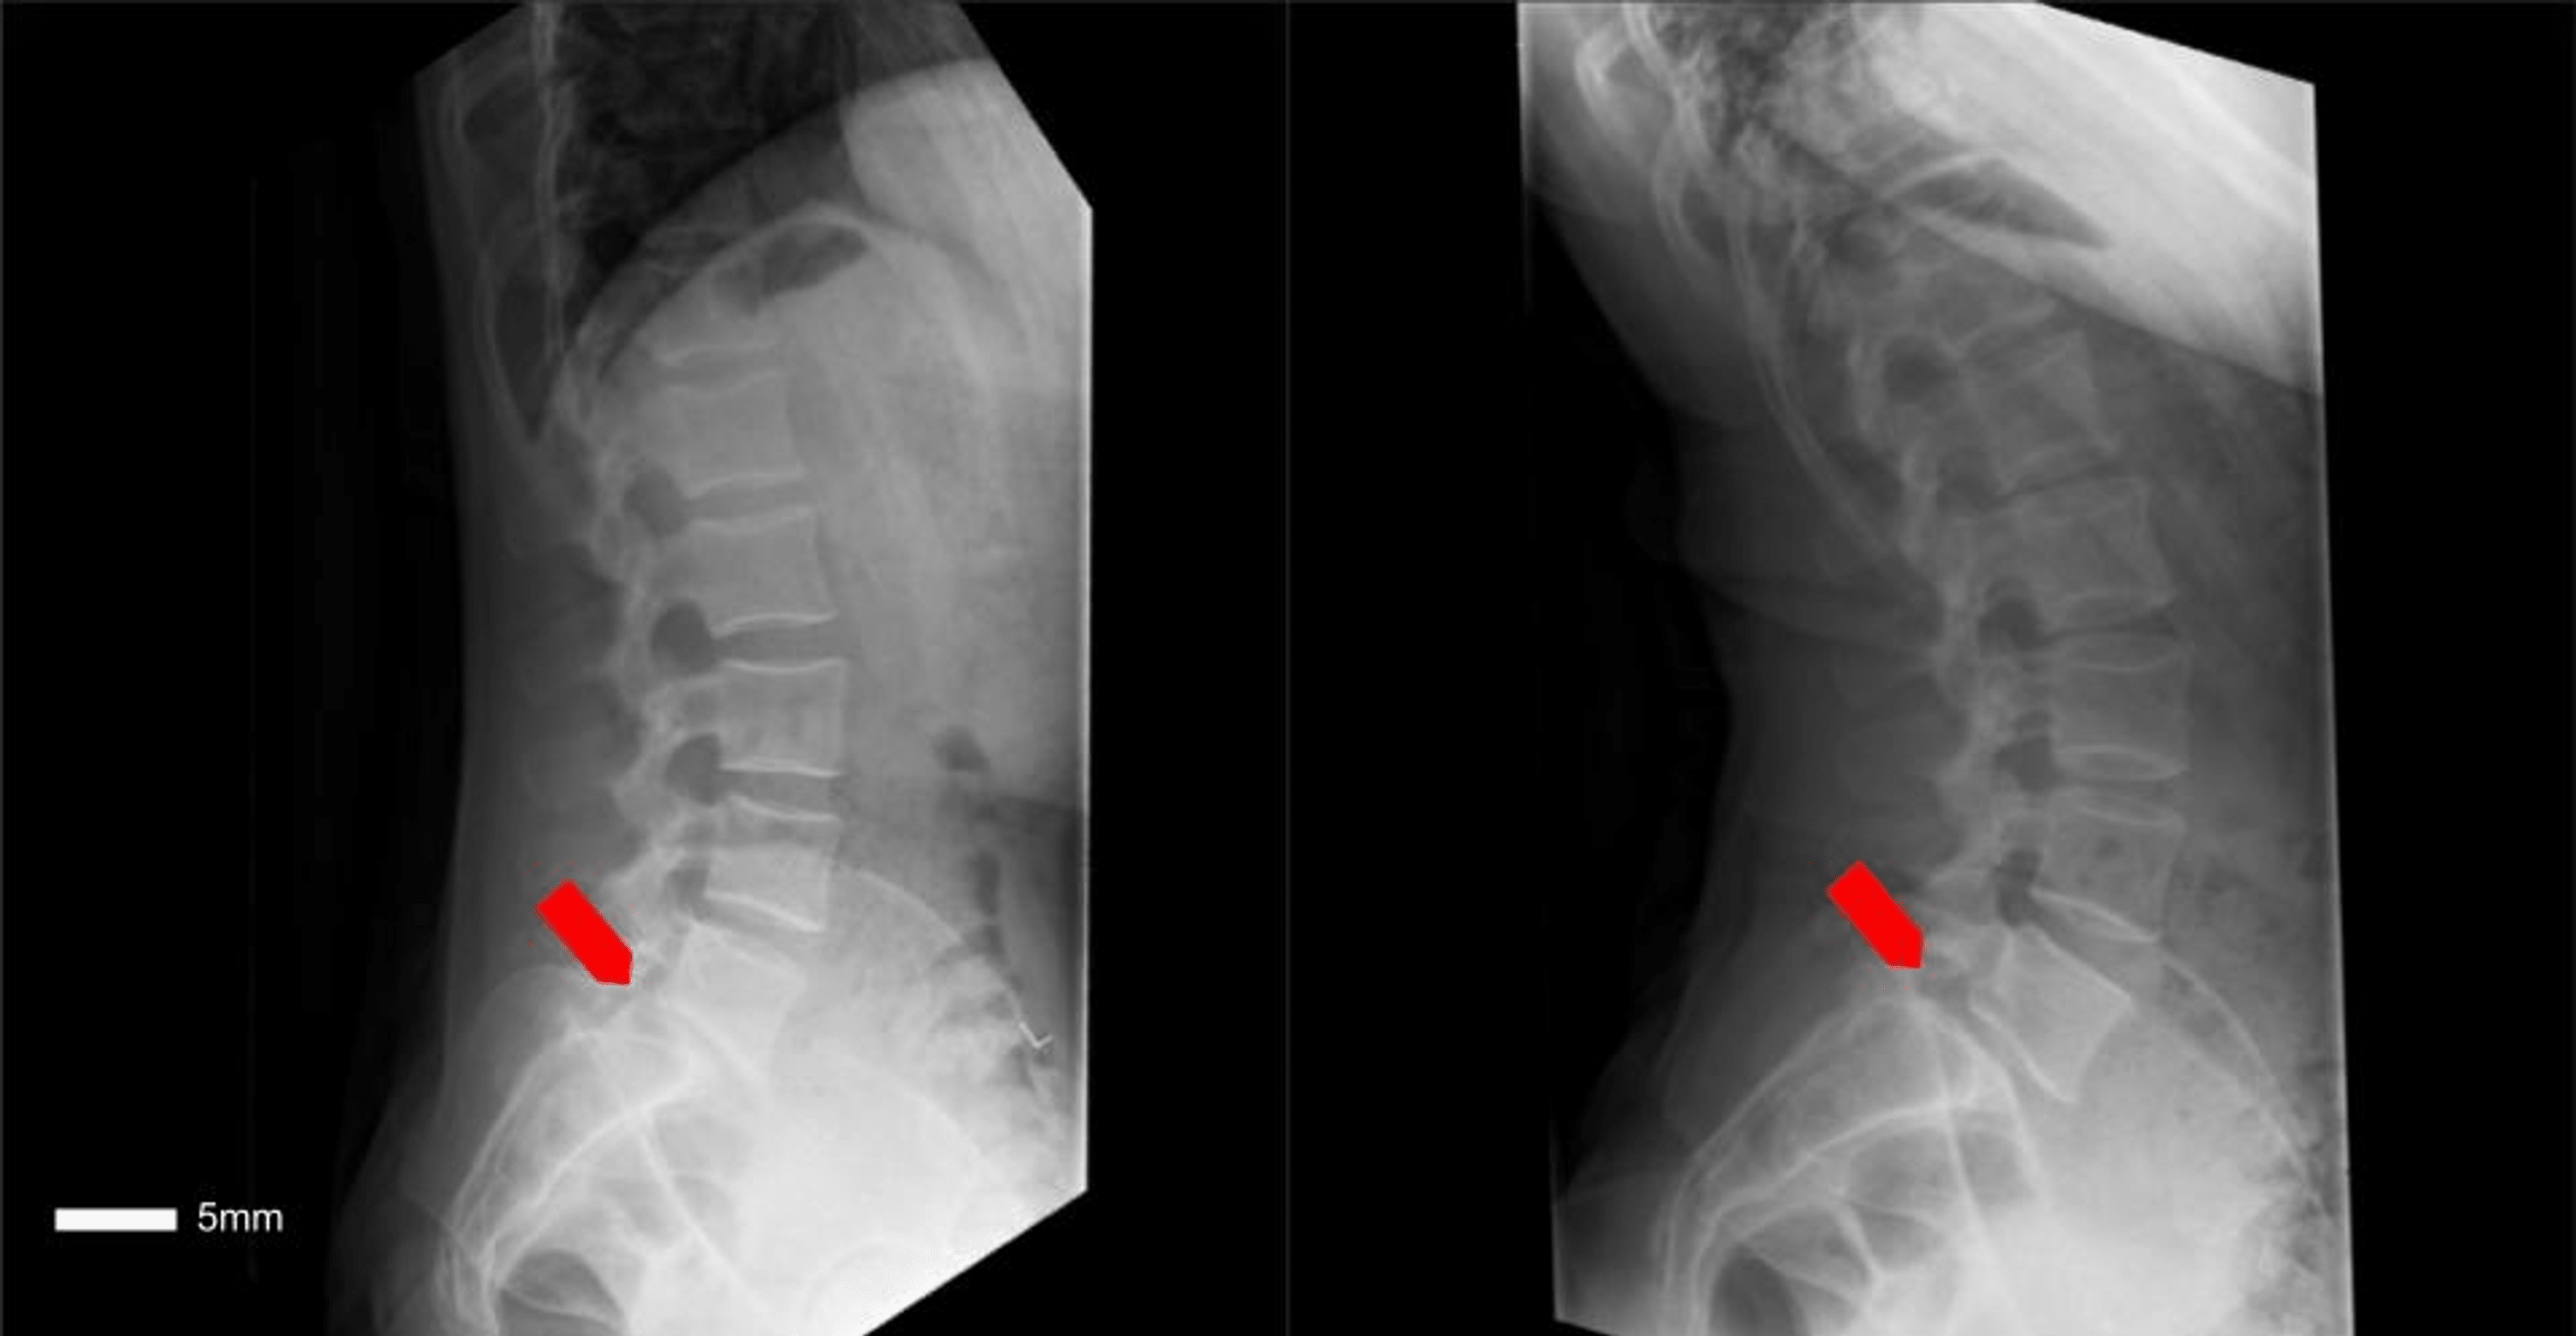

Preoperative flexion and extension of lumbar spine (Left image) Lateral... Download Scientific Flexion Extension Spondylolisthesis Flexion and extension lateral lumbar radiographs can identify the degree of instability. Mri studies can be helpful for central or foraminal stenosis. Patients typically have intermittent and localized low back pain for lumbar spondylolisthesis and localized neck pain for cervical. Serial standing lateral radiographs obtained in. To assess dynamic instability, flexion and extension views should be obtained. A key component. Flexion Extension Spondylolisthesis.

A 71yearold female patient with L4/L5 degenerative spondylolisthesis.... Download Scientific Flexion Extension Spondylolisthesis Mri studies can be helpful for central or foraminal stenosis. Patients typically have intermittent and localized low back pain for lumbar spondylolisthesis and localized neck pain for cervical. To assess dynamic instability, flexion and extension views should be obtained. Serial standing lateral radiographs obtained in. A key component to radiographic evaluation is obtaining flexion/extension films, which illustrates vertebral segment stability.. Flexion Extension Spondylolisthesis.